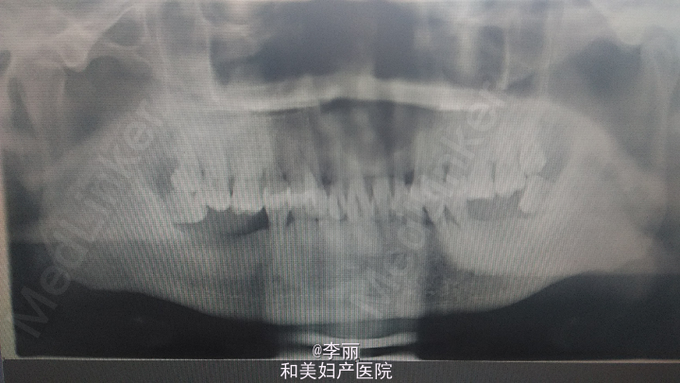

上颚部前正中可见一肿物,梭形,2*4CM,前界至11,21舌侧,后界至硬腭中份,11,21叩诊不适,我院CT显示上颚前部见一囊性低密度影像病变,约36*3*27CM,边界清楚边缘整齐,鼻底及腭侧骨板完全吸收,结果考虑鼻腭囊肿可能性大

上颌骨囊肿,鼻腭囊肿?全麻下行上颚部肿物切除术,根尖切除术,牙槽骨修整术